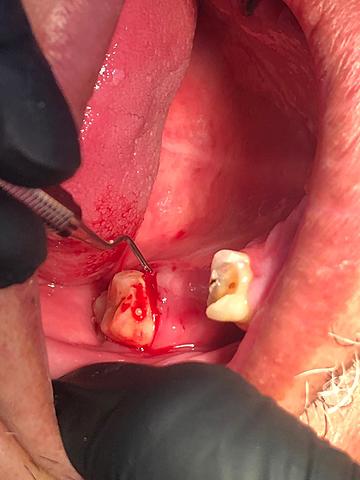

• EXODONCIAS

Se realizará extracción de restos radiculares 1.3, 1.4, 1.5 Y 1.6